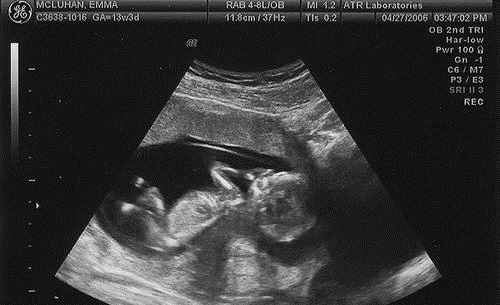

Первый скрининг во время беременности — это ключевой этап, который дает возможность оценить состояние плода и выявить потенциальные аномалии. Обычно он осуществляется на сроке от 11 до 14 недель. Врач проводит ультразвуковое исследование, измеряя размеры плода и проверяя его анатомические особенности. Также анализируется уровень гормонов в крови, что помогает оценить риск хромосомных заболеваний.

Первый скрининг при беременности является важным этапом, который позволяет оценить здоровье плода и выявить возможные аномалии. Обычно его проводят на сроке 11-14 недель. Процедура включает ультразвуковое исследование и анализ крови на определение уровня гормонов и белков. УЗИ помогает оценить размеры плода, его сердцебиение и наличие хромосомных аномалий. Подготовка к скринингу не требует особых усилий: достаточно прийти на процедуру с полным мочевым пузырем.

Отличие в проведении первого скринингового обследования заключается в использовании трансвагинального способа введения датчика УЗИ. Этот способ проводится путем введения датчика во влагалище.

Трансвагинальное УЗИ проводится только в 1 триместре беременности. К 16 неделе высота матки заметно увеличивается, плод становится крупнее, что позволяет при обследованиях 2-го, 3-го скрининга ограничиться только трансабдоминальным способом.

Как проводится обследование

Первый скрининг при беременности, как делают, решает врач на основании уточненного срока беременности. Контакт датчика с телом облегчается при помощи специального геля на основе глицерина, который наносится на кожу. Матка с имеющейся околоплодной жидкостью активно проводит звуки.

Это позволяет изучать развитие плода, прослушивать его сердцебиение, регистрировать патологии органов и систем. Неудобное положение плода в матке может затруднить всестороннее исследование. В таком случае, женщине необходимо легкими активными движениями спровоцировать ребенка на изменение позы.

Обследование проводится в 2 этапа:

УЗИ — исследование:

- Трансабдоминальный способ процедуры. Он абсолютно безболезненный, но недостаточно точный.

- Трансвагинальный способ. Для него не требуется специальная подготовка, наполненный мочевой пузырь. Однако следует отказаться от газообразующей пищи. Обзор плода и матки более качественный, по сравнению с трансабдоминальным способом, поскольку производится внутри тела женщины. Минусом является дискомфорт, при введении датчика во влагалище.